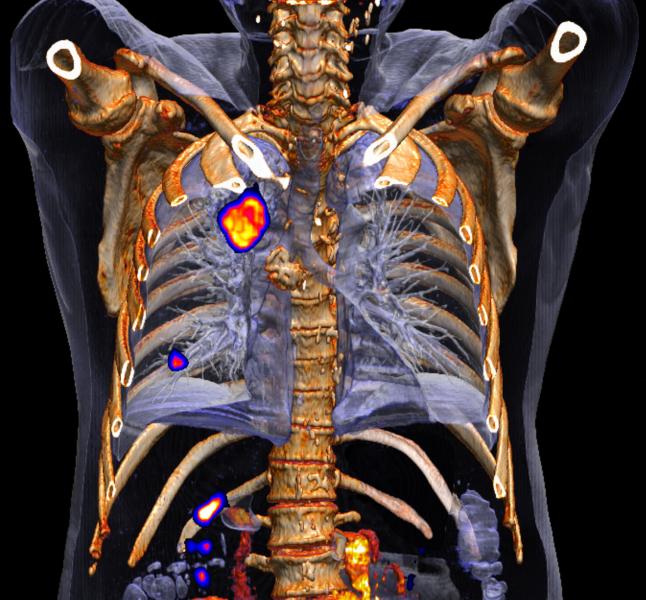

Image courtesy Siemens Healthcare

The good news for molecular imaging is that the latest generation of PET/CT can visualize more and subtler signs of disease. Even better, these souped-up machines can more precisely measure standard uptake values (SUVs). This adds credence to their role in quantifying what has long been a subjective process of diagnosing, prognosing and following patients.

Scanning patients on newer, more powerful PET/CTs can reveal lesions that were overlooked earlier, giving the appearance that a therapy is ineffective or the disease has returned. This may happen when the latest images show what were too small to spot on less powerful machines. Additionally, the quantitative measurements may be higher because the latest equipment is more sensitive. Different protocols, some of which may be introduced with the availability of new equipment, may further skew interpretations.

Quantitative measurements — standard uptake values — can be particularly vexing. Ones recorded prior to oncologic therapy provide the baselines against which those acquired during and after therapy are compared. SUVs may be used to set PERCIST (PET response criteria in solid tumors) thresholds for individual patients. Research has documented that an increase of 30 percent or more above the PERCIST threshold indicates poor patient response and that a change in therapy should be considered. Conversely, a decline of 30 percent or more indicates a likely positive effect and that the therapy is working.